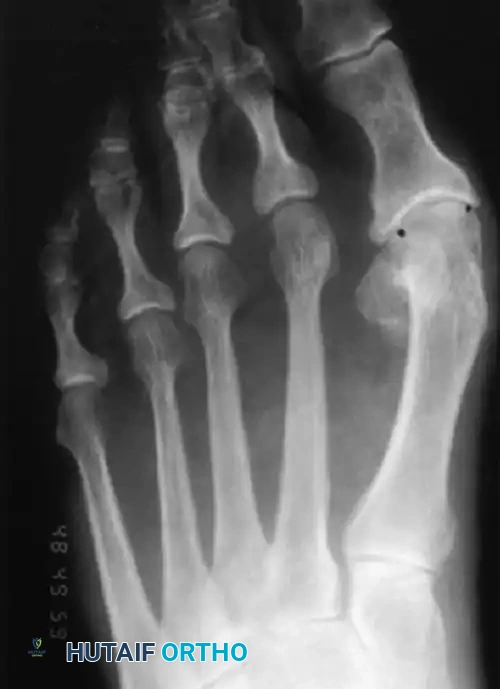

Figure 81-73: Anteroposterior weight-bearing radiograph in an elderly woman, 20 years after a McBride bunionectomy. In reality, this is a congruous hallux valgus that assumed its normal position on the first metatarsal head after a soft tissue realignment for hallux valgus. A biplanar correcting distal metatarsal osteotomy is needed to address the abnormal DMAA.